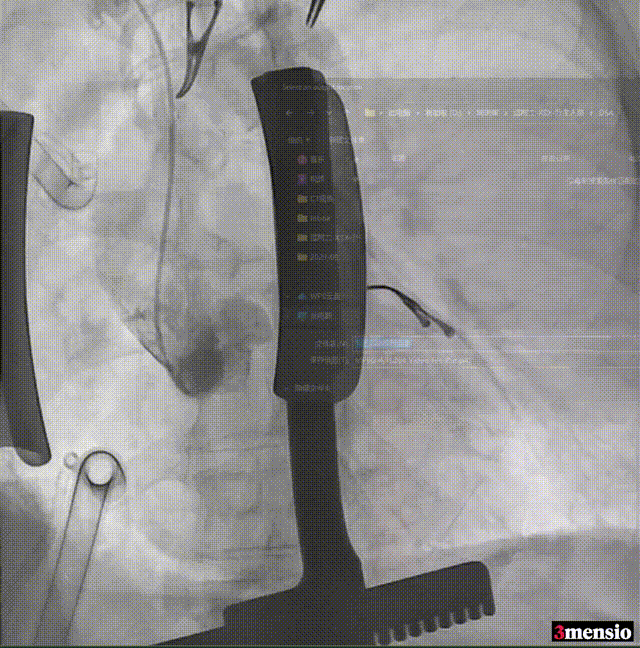

手术过程

手术流程概览:

通道建立

25cm、20F 大鞘置入

主动脉根部造影

直头导丝跨瓣

交换预塑形小弯导丝

20mm球囊预扩张,无腰无漏

AV26 瓣膜初始定位

工作位造影评估

瓣膜脱钩

中度反流,需球囊后扩

22mm 球囊后扩

最终造影,微量反流,无瓣周漏